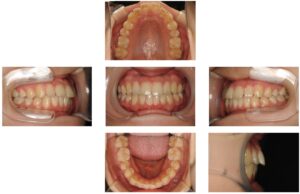

出っ歯の改善〔裏側矯正・福岡・天神〕

| 主訴 | 前歯が出ている |

| 年齢 | 23歳 |

| 診断 | 叢生 |

| 治療内容 | フルリンガルブラケット |

| 上顎左右4、下顎左右5抜歯 | |

| 治療期間 | 2年10か月 |

| 費用 | 1,150,000円 |